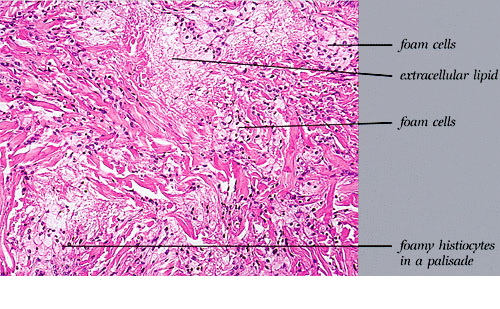

Epidermolysis bullosa acquisita = انحلال البشرة الفقاعي المكتسب Epidermolysis Bullosa Acquisita Classically, EBA is a noninherited disorder of acquired skin fragility. This presentation of EBA was the only one recognized until later. Blisters develop on noninflammatory bases with a predilection for acral areas. Scarring and milia formation ensue. A characteristic nail dystrophy and alopecia are […]